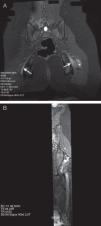

Magnetic resonance (MR) neurography refers to a set of techniques that enable the structure of the peripheral nerves and nerve plexuses to be evaluated optimally. New two-dimensional and three-dimensional neurographic sequences, in particular in 3T scanners, achieve excellent contrast between the nerve and perineural structures. MR neurography makes it possible to distinguish between the normal fascicular pattern of the nerve and anomalies like inflammation, trauma, and tumor that can affect nerves. In this article, we describe the structure of the sciatic nerve, its characteristics on MR neurography, and the most common diseases that affect it.